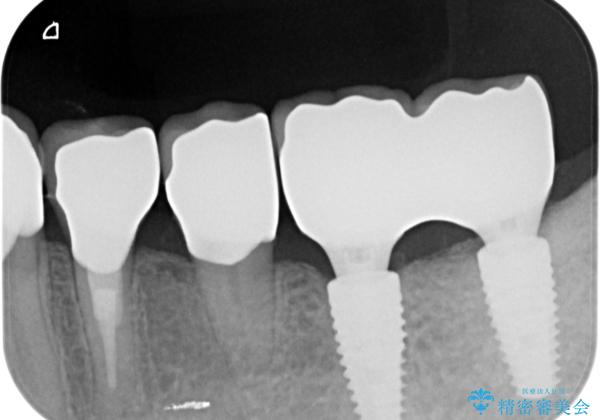

- 他院で約10年前に入れたブリッジのすり減り、虫歯の再発、審美性の改善を求めて来院されました。

ブリッジ、虫歯を丁寧に除去したのち精密なジルコニアクラウンの作製を行い咬合機能をしっかりと回復します。

ブリッジの支台となる後方臼歯は清掃性が悪く虫歯が大きくなっていたため、抜去を行いインプラントを用いた治療としました。